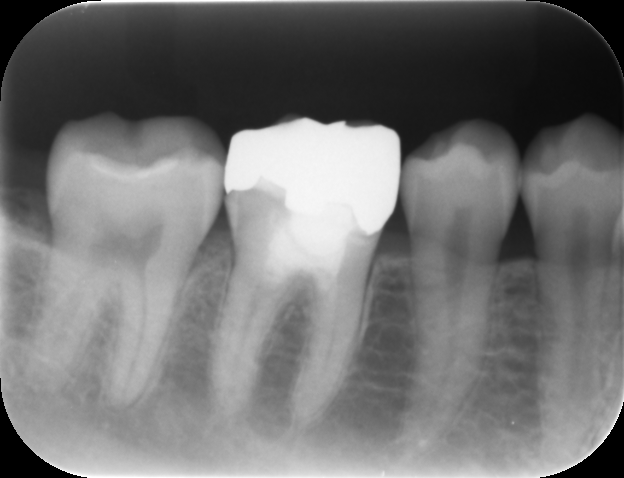

根管充填後レントゲンおよびCT画像です。

症状が消失したため、ガッタパーチャとバイオセラミックシーラーにて根管充填を行いました。炎症が強かったため、歯槽骨の吸収の範囲が術前よりも広がっています(矢印)。